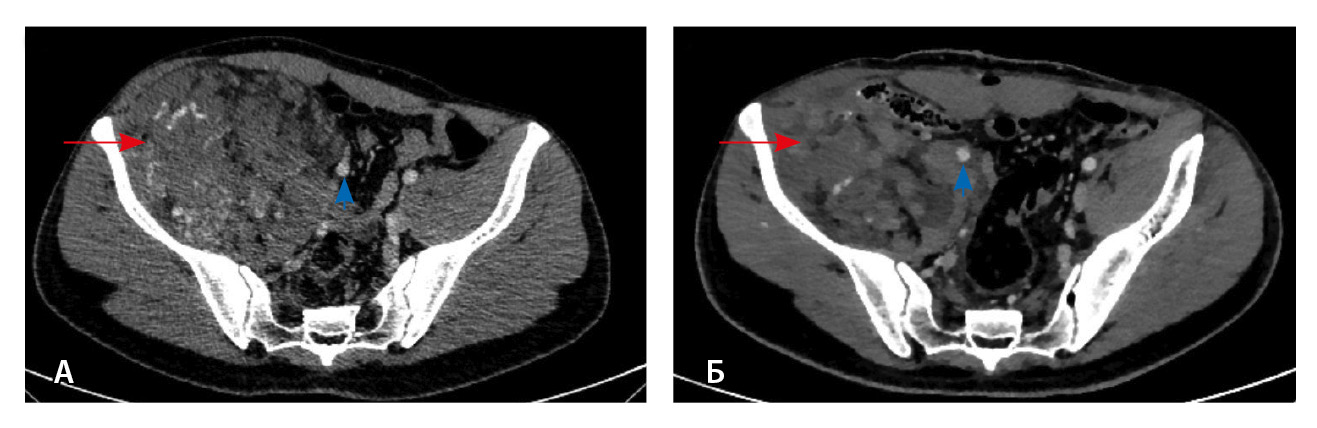

Рис. 2. Мультиспиральная компьютерная томография органов брюшной полости и забрюшинного пространства, режим костного окна. Кортикальный слой правой подвздошной кости прослеживается равномерно на всем протяжении, без признаков деструкции (стрелки)

Близкое расположение внутримышечных гемангиом к костям приводит к контактным изменениям последних. Методами лучевой диагностики выделяют три типа изменений костных структур – периостальные, кортикальные и медуллярные. Близость расположения образования к кости статически значимо коррелирует с любым типом костной реакции, а размер образования – лишь с медуллярным [14]. Агрессивный тип периостальной реакции и деструкция кортикального слоя могут быть ошибочно приняты за первичную опухоль кости [6, 15]. Однако эти изменения факультативны: так, в нашем исследовании никаких изменений костных структур отмечено не было.